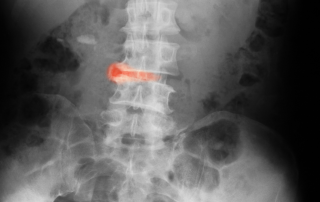

Postür Bozukluğunun Bel Ağrısına Etkileri

İnsanların neredeyse çoğu bel bölgesinde ağrılarla boğuşmaktadır. Bu ağrıların en önemli sebebi postur bozukluğuna bağlıdır.